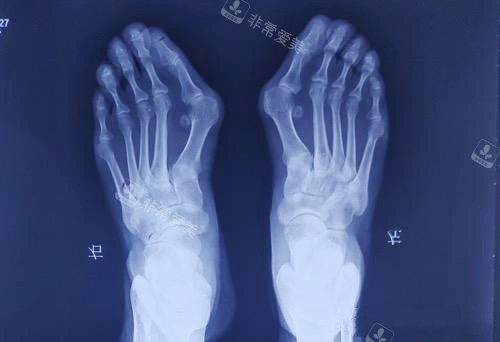

怀着紧张又期待的心情,我来到了韩国的整形医院。医院的环境非常舒适,工作人员也都非常热情和正规。在面诊时,医生仔细地检查了我的脚部情况,用正规的仪器进行了详细的测量和分析。

医生根据我的具体情况,制定了个性化的手术方案。他耐心地向我解释了手术的过程、风险和术后注意事项,让我对手术有了更多方面的了解。我也向医生提出了自己的疑问和担忧,医生都一一进行了解答,让我心里踏实了许多。